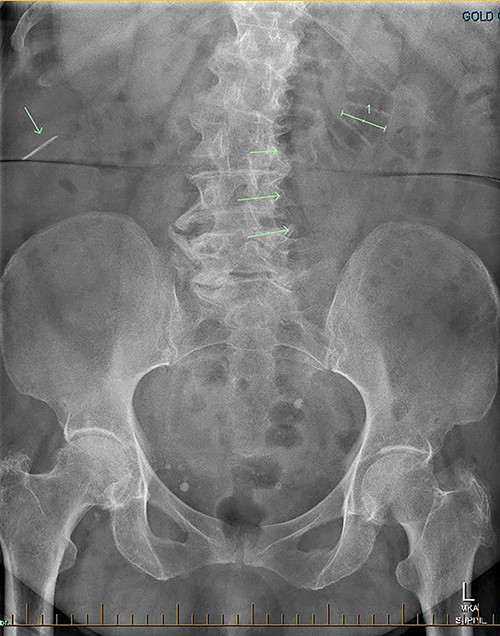

Patient RF a 74-year-old lady with a background of obesity and dyslipidaemia was admitted under the acute surgical care team after experiencing several weeks of diarrhoea, vomiting and a generalized grumbling abdominal pain. Initial abdominal plain films showed a FB in the right middle abdomen (Fig. 3). A follow-up CT was able to highlight this linear hyperdensity which correlated in location to the plain radiographs (Fig. 4). Her laboratory markers were as follows WCC 14 × 109/L, neutrophil count 13 × 109/L, C-reactive protein 57 mg/L. RF herself could not recall a history of FB ingestion. Initially the medical teams had presumed that the FB could have been a fragment of the patients’ denture. RF was placed on a clear fluid diet and daily serial plain films were performed to observe for progression of the FB. On Day 2, interestingly the FB was no longer present on plain films.

Secondly, as shown in the three cases, unless the BC is calcified, abdominal plain films are not a reliable method of tracking nor diagnosing BC ingestion [9–13]. CT is more sensitive, with a sensitivity rate of 67%, but is not consistently reliable on its own [6, 7]. Reconstructed 3D imaging is effective in identifying BCs. Most BCs are made of low-density polystyrene, a type of versatile solid plastic, which are not readily identified on plain film imaging [14, 15]. This non-degradable plastic means that it is usually only a matter of time before a patient develops a complication.